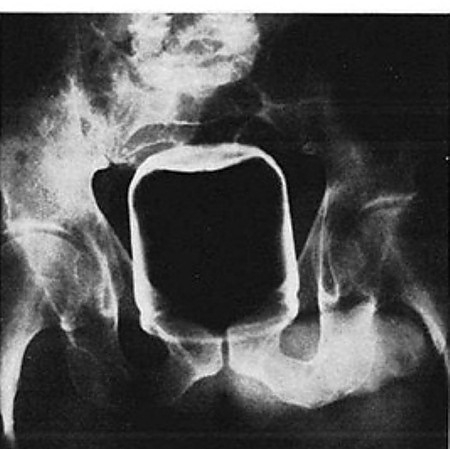

Malum Bölgelerine Kazayla Giren Nesneler Sonucu Acile Kaldırılmış İnsanların 15 Röntgen Görüntüsü Bu nesnelerin orada olmasının mantıklı hiçbir alakası yok. Büyük ihtimalle bir kaza sonucu bu durum oluşmuştur. Aksini düşünmek bile istemiyorum. Foto Galerimizin devamını görmek için Lütfen sonraki sayfaya geçiniz..